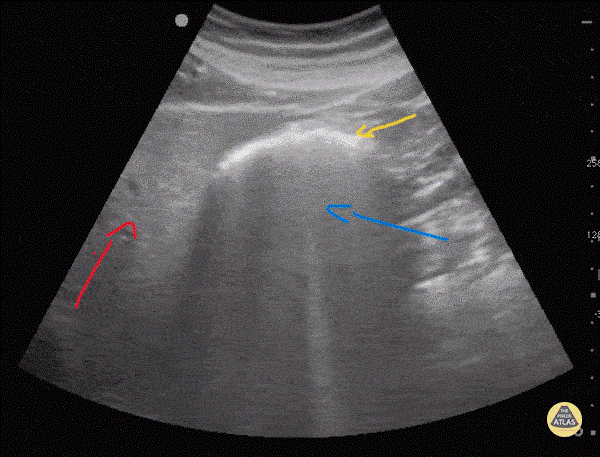

Bélgáz

A kép bal oldalán piros nyíllal jelölve látjuk a májat, mellette figyelhető meg egy bélszakasz (sárga nyíl) ami mögött függönyszerűen terül el az úgynevezett hangárnyék (kék nyíl) ami kitakarja a mögötte lévő szerveket. Ezt a hangárnyékot a belekben lévő bélgáz okozza, ami műterméket okoz az ultrahang képeken.